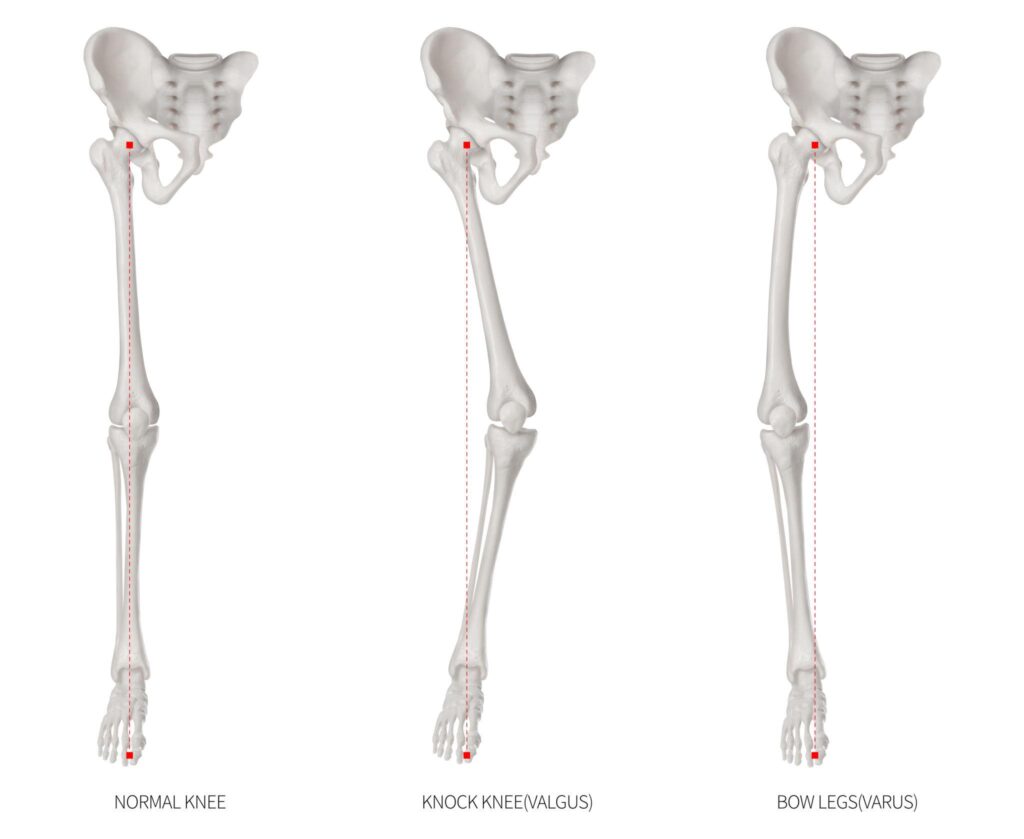

Bowing of the legs is a common knee alignment condition medically known as genu varum, or varus deformity. In this condition, the legs curve outward at the knees, giving a bow-shaped appearance. It occurs when the tibia (shin bone) turns inward instead of aligning properly with the femur (thigh bone), causing the knees to move away from the body’s midline.

The alignment between the femur and tibia is called tibiofemoral alignment. Ideally, this alignment forms a straight 180-degree angle. When the angle deviates, even slightly, it can go unnoticed for years before symptoms appear.